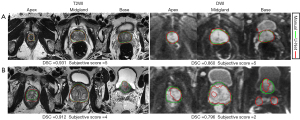

The qualitative analysis results for the internal testing cohort and PXtest cohort are presented in Table 4. In the internal testing cohort, the subjective scores were greater than or equal to 4 in 100% of cases for T2WI (92.6% with a score of 5 and 7.4% with a score of 4), and the scores were greater than or equal to 4 in 97.9% of cases for DWI (89.5% with a score of 5 and 8.4% with a score of 4). In the PXtest cohort, for T2WI, 79.4% of cases were rated as a score of 5, 19.1% of cases were rated as a score of 4, and only 2 cases (1.4%) were rated as a score of 3. Therefore, 98.6% of segmentation results on T2WI were considered clinically acceptable. For DWI results, most cases (102/141, 72.3%) reached satisfying subjective scores. Specifically, 51.8% of cases were rated as a score of 5, and 20.6% of cases were rated as a score of 4. Figure 3 shows 2 examples of the CNN segmentation results from the PXtest cohort with corresponding DSC and subjective scores to illustrate the models’ clinical utility with both quantitative and qualitative analyse.

Figure 3 Examples of segmentation results. (A) In this case, the 3-dimensional U-Net model (red line) showed a good overlap with the manual segmentation (green line) in the apex, midgland, and base (from left to right) of the prostate on both T2WI and DWI, with an overall DSC of 0.931 for T2WI and 0.860 for DWI. The subjective scores for both T2WI and DWI segmentation results were 5. (B) In this case, the overall DSC was 0.912 on T2WI and 0.796 for DWI. The subjective score for T2WI was 4, which required minor modification in the apex and base of the prostate. As for DWI images, the model showed a poor overlap with the manual segmentation, with a subjective score of 2. T2WI, T2-weighted images; DWI, diffusion-weighted images; DSC, Dice similarity coefficient.